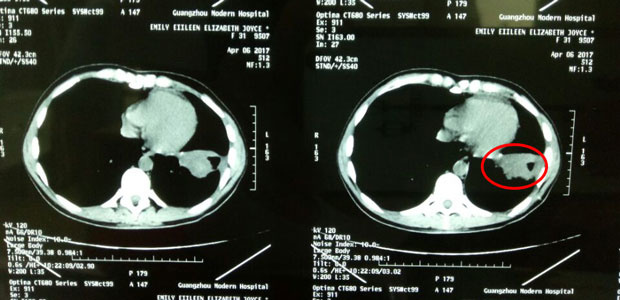

In April, tumors in her lung

When Emily was admitted into St. Stamford Modern Cancer Hospital Guangzhou, she was very weak. She kept coughing day and night and can hardly walk or lie down. She had difficulty in breath due to the fluid in her lungs. She felt like a drowning man. After detailed check-up, doctors first helped drained out 3 liters of fluid, then interventional therapy was conducted straight away in her lung to kill the tumors. Soon after, tumors began to die off, her cough was cured and she regained her physical strength to walk all day. Emily underwent cryotherapy later, which she said was amazing and very easy. She coughed up part of the dead tumor four days after the cryotherapy. Till now, she has experienced three sessions of interventional therapy and two sessions of cryotherapy. The latest CT scan result showed that tumors in her lungs were much smaller, and the largest one already shrank by 4 cm.